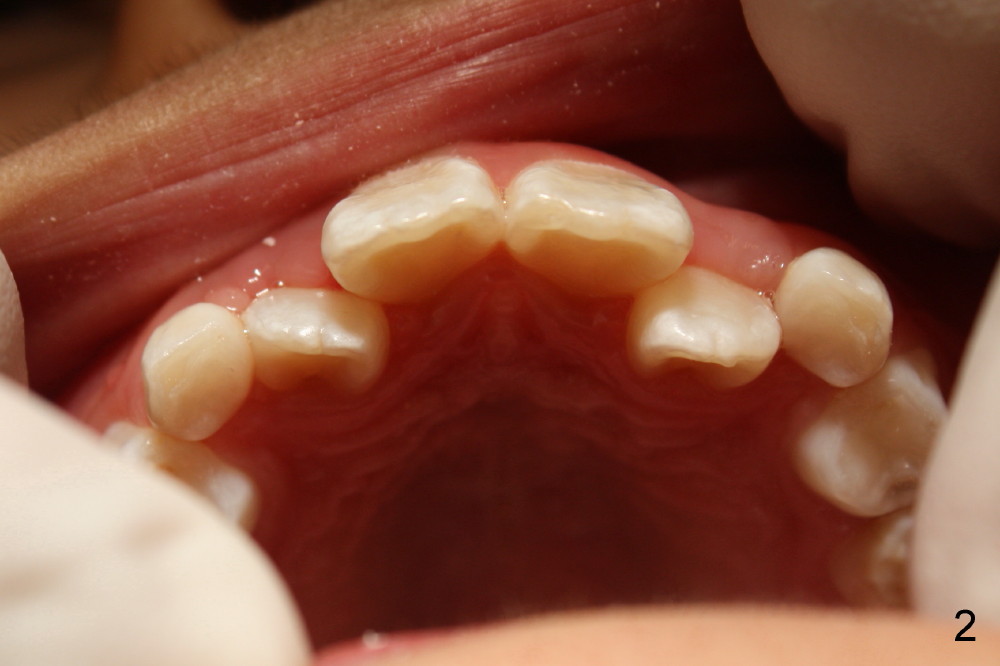

Six months earlier, the tooth #7 is erupting lingually. Now at the age of 8, both of the upper lateral incisors are in cross bite (Fig.1*). It appears that the cross bite is due to jaw deficiency in anteroposterior direction. In fact, these two laterals are blocked because there is not enough space transversely (Fig.2). Posterior occlusion is Class I bilaterally (Fig.3,4). The lower incisors are also crowded. Therefore early comprehensive orthodontic treatment has the most important component: palatal expander. In our previous case, unilateral cross bite resolves rapidly after the palate is expanded.